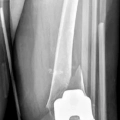

Ο Σακελλαρίου Βασίλειος είναι Ορθοπαιδικός Χειρουργός με ιατρεία στη Νέα Σμύρνη "Athens Orthopedic Experts", στο Μαρούσι (εντός της Ορθοπαιδικής Κλινικής "Osteon") και στη Γλυφάδα (εντός της Ορθοπαιδικής Κλινικής "Osteon"). Έχει ανακηρυχθεί Διδάκτωρ του Εθνικού και Καποδιστριακού Πανεπιστημίου Αθηνών μετά από εκπόνηση διατριβής με θέμα "Ανακατασκευή οστικών ελλειμμάτων διαφύσεως μακρών οστών. Συγκριτική εμβιομηχανική μελέτη σταθερότητας με χρήση μεταλλικών προθέσεων τιτανίου έναντι αλλομοσχευμάτων", ενώ είναι απόφοιτος της Ιατρικής Σχολής του ιδίου Πανεπιστημίου. Κατέχει μεταπτυχιακό τίτλο σπουδών στα "Μεταβολικά Νοσήματα των Οστών" από το Εθνικό και Καποδιστριακό Πανεπιστήμιο Αθηνών. Μετά το πέρας των προπτυχιακών σπουδών του, ειδικεύτηκε στη Γενική Χειρουργική στο Γενικό Νοσοκομείο Λιβαδειάς και στο Γενικό Νοσοκομείο Άρτας. Κατόπιν, απέκτησε την Ιατρική Ειδικότητα της Ορθοπαιδικής - Τραυματολογίας από την Α' Ορθοπαιδική Κλινική του Πανεπιστημιακού Γενικού Νοσοκομείου - Αττικόν. Κατά τη διάρκεια της ειδίκευσής του, εκπαιδεύτηκε στη Μικροχειρουργική στο Γενικό Νοσοκομείο Αττικής - ΚΑΤ, καθώς και στην Παιδοορθοπαιδική και στις Αθλητικές Κακώσεις στο Πανεπιστημιακό Γενικό Νοσοκομείο - Αττικόν. Στην πορεία της επαγγελματικής του σταδιοδρομίας, υπήρξε Επισκέπτης Ιατρός (Visiting Clinician) στο Τμήμα Ορθοπαιδικής της Mayo Clinic στις ΗΠΑ, όπου εν συνεχεία έλαβε μεταδιδακτορικό τίτλο σπουδών από το εργαστήριο εμβιομηχανικής και ανάλυσης κίνησης. Επιπλέον, έχει εργαστεί ως Έμμισθος Κλινικός Υπότροφος (Clinical Fellow) στον Τομέα Επανορθωτικής Χειρουργικής Ενηλίκων - Χειρουργικής των Μεγάλων Αρθρώσεων Ισχίου και Γόνατος στο Hospital for Special Surgery (HSS), ενώ διετέλεσε Διευθυντής της Ορθοπαιδικής Κλινικής στο Νοσοκομείο "Mediterraneo" και στην Ευρωκλινική Αθηνών. Μέχρι και σήμερα, είναι Επικεφαλής του Τμήματος Επανορθωτικής και Ελάχιστα Επεμβατικής Χειρουργικής Ισχίου - Γόνατος στην Ορθοπαιδική Κλινική "Osteon" και κατέχει τη θέση του Διευθυντή Ελάχιστα Επεμβατικής Χειρουργικής (MIS) Ισχίου - Γόνατος και Μυοσκελετικής Ογκολογίας στην Ορθοπαιδική Κλινική του Ιατρικού Κέντρου Αθηνών. Παράλληλα, διατελεί Πανεπιστημιακός Υπότροφος με εξειδίκευση στη "Χειρουργική Ισχίου και Γόνατος" στην Α' Ορθοπαιδική Κλινική του Εθνικού και Καποδιστριακού Πανεπιστημίου Αθηνών στο Πανεπιστημιακό Γενικό Νοσοκομείο - Αττικόν. Στο πλαίσιο της διαρκούς εκπαίδευσης και επιμόρφωσής του, συμμετέχει τακτικά σε επιστημονικά συνέδρια τόσο στην Ελλάδα όσο και το εξωτερικό και έχει στο ενεργητικό του πολυάριθμες δημοσιεύσεις σε έγκριτα ιατρικά περιοδικά.

Αρθροπλαστική γόνατος

Αρθροπλαστική ισχίου

Αρθροπλαστική ελάχιστης επεμβατικότητας